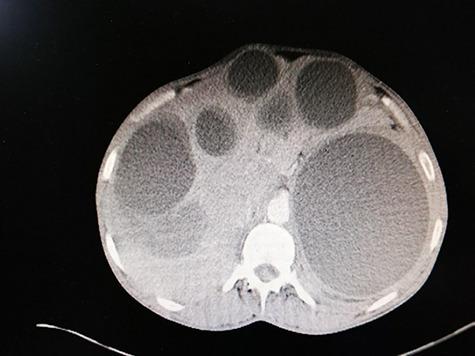

Hydatid disease (HD) is an infection with the metacestode stage of the tapeworm . It is commonly seen in South America, The Middle East, Eastern Mediterranean, Africa and China. Hydatid cysts usually affect the liver followed by the lungs. Involvement in other organs has been reported. However, in the majority of the cases, cysts are localized in one organ or one region. We report a rare case of a 36-year-old woman who presented to the hospital in Syria with long-standing history of non-specific abdominal pain. Computerized tomography showed several hydatid cysts in the liver, spleen, left lung, mediastinum (adjacent to the aortic arch), both breasts and above the right gluteal muscles.

包虫病(HD)是由绦虫的中绦期幼虫感染所致。该病常见于南美洲、中东、东地中海地区、非洲和中国。包虫囊肿通常首先累及肝脏,其次是肺。也有累及其他器官的报道。然而,在大多数病例中,囊肿局限于一个器官或一个区域。我们报告一例罕见病例,一名36岁女性因长期非特异性腹痛就诊于叙利亚一家医院。计算机断层扫描显示肝脏、脾脏、左肺、纵隔(毗邻主动脉弓)、双侧乳房及右臀肌上方有多个包虫囊肿。